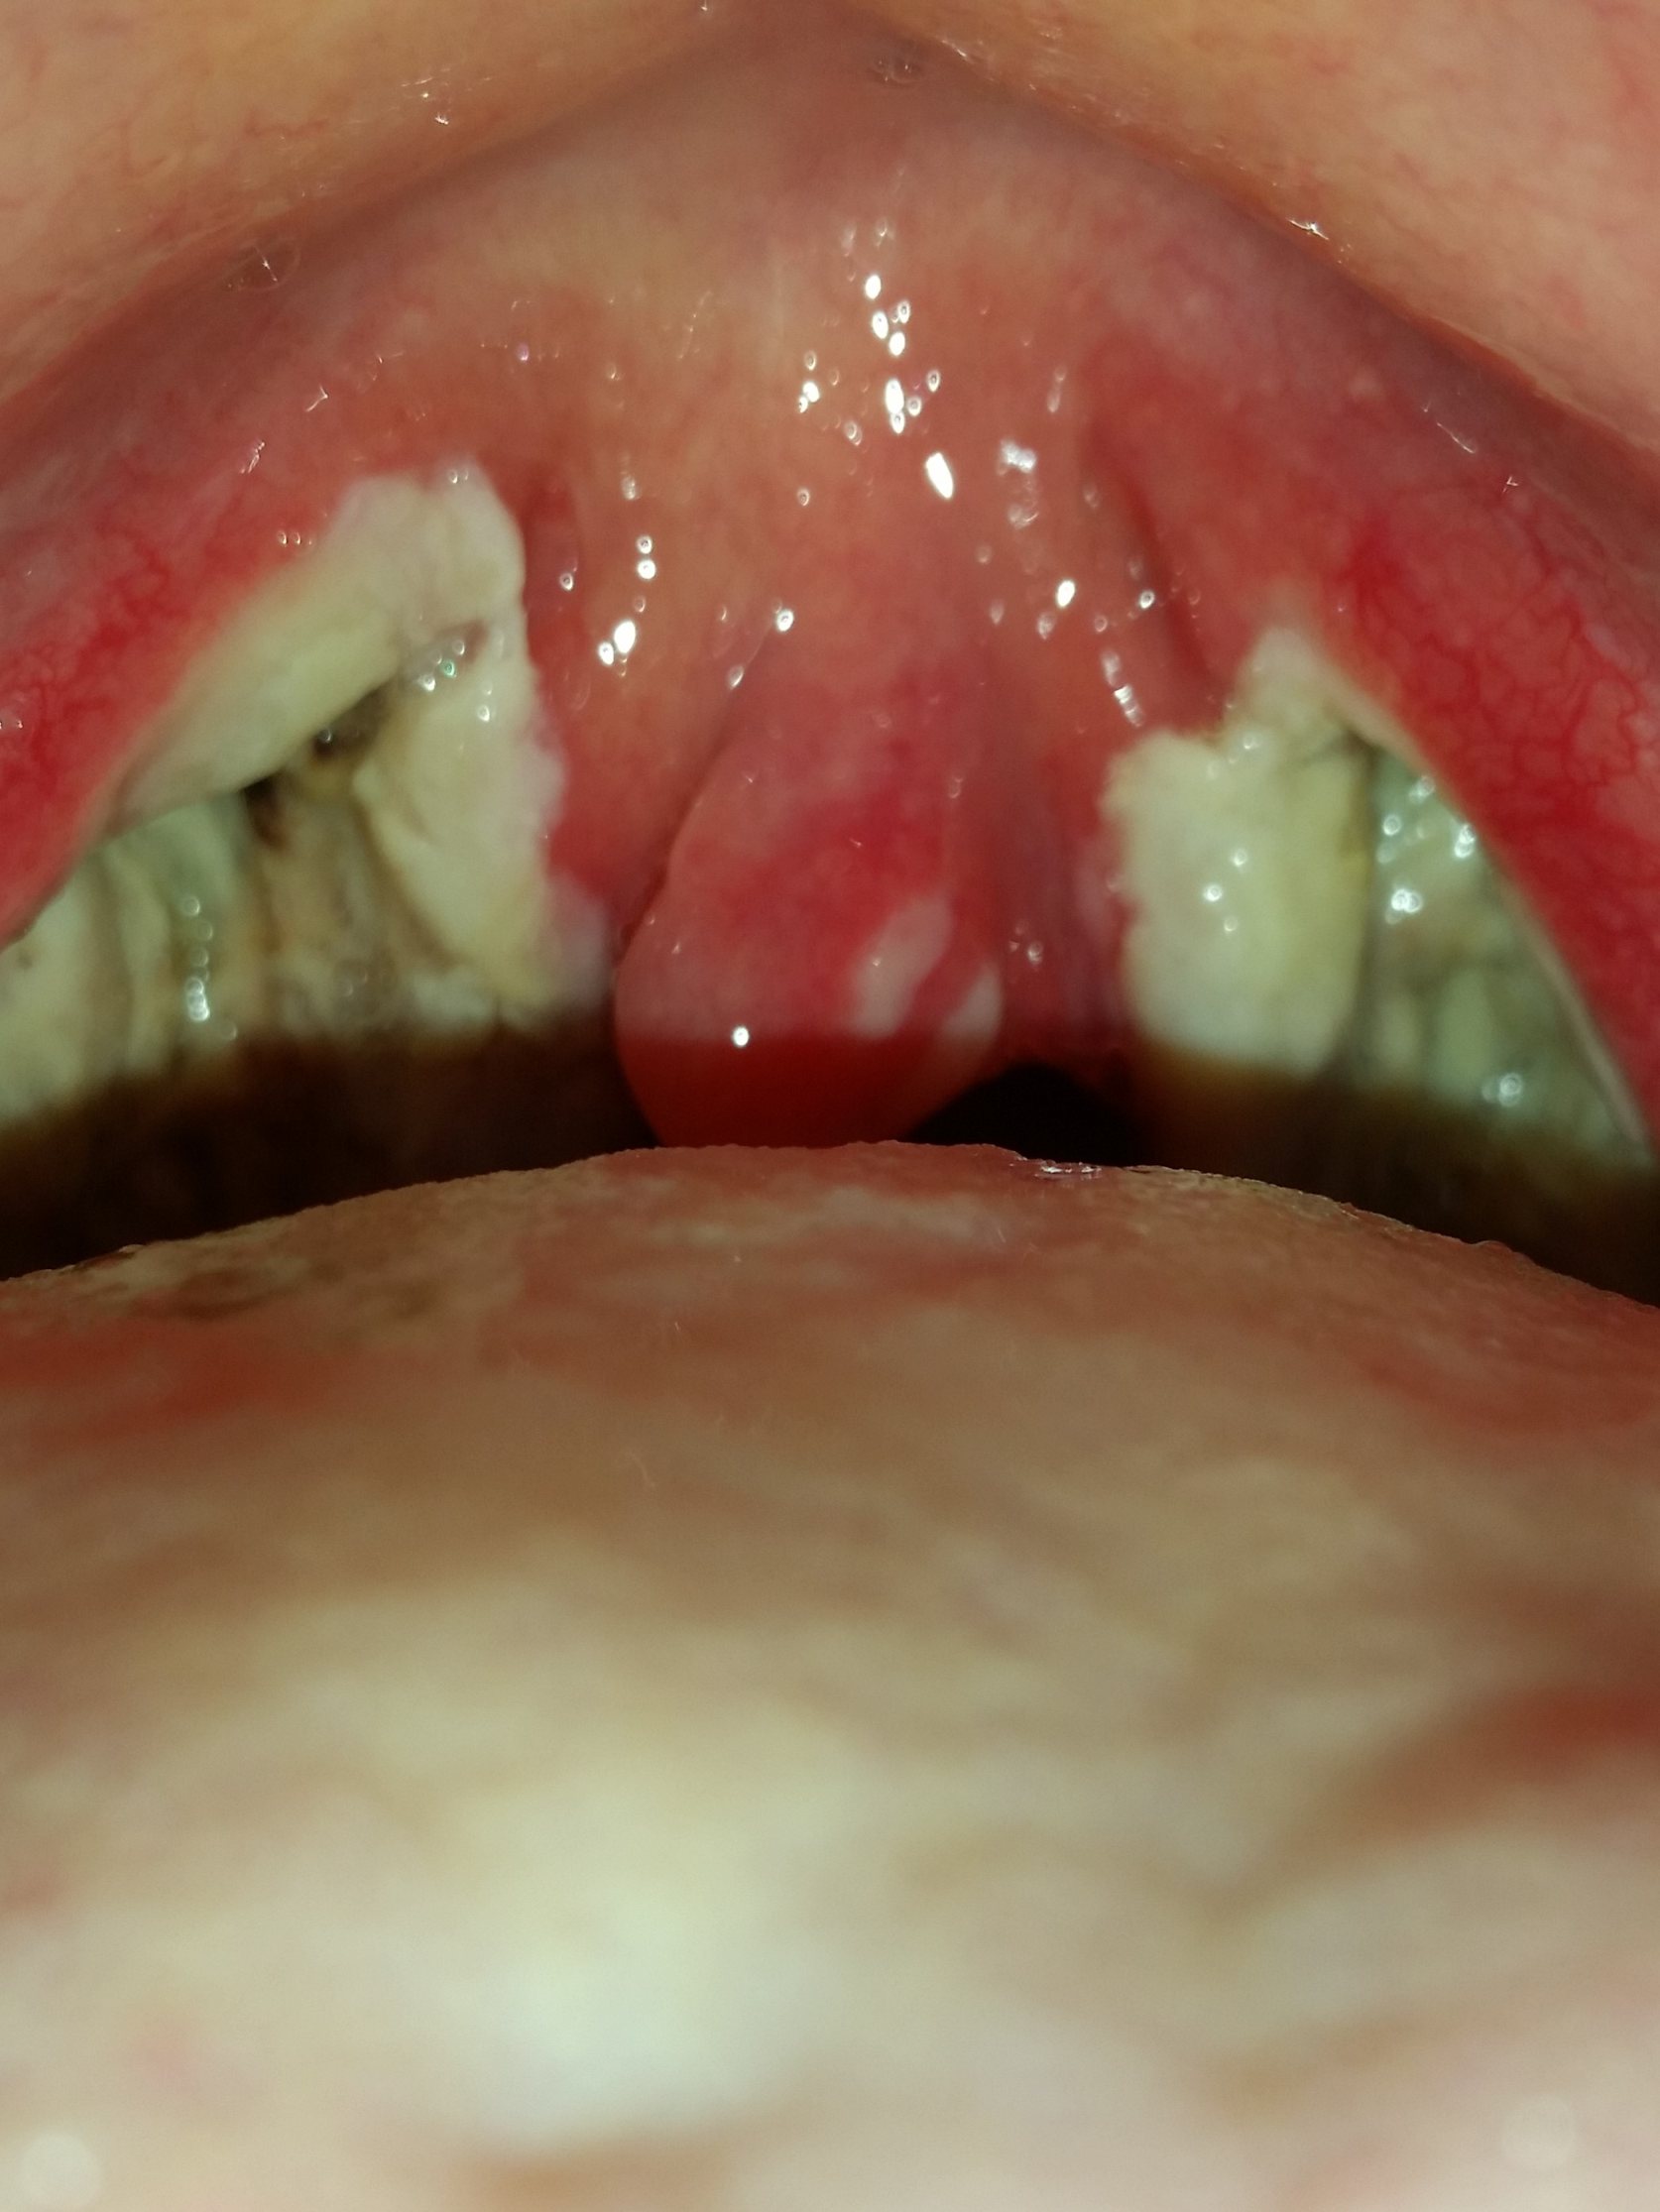

Mandel OP – Bilder Dokumentation Heilungsprozess

- Mandeloperation Tag 4

- Mandeloperation Tag 5

Nach der Operation bildeten sich direkt die weiß, grünlichen Beläge (Fibrinbeläge).

Bis sich die Beläge lösten hatte ich einen leicht „fauligen Mundgeruch“.

Ab dem Tag 9 lösten sich langsam die Beläge. (Ein ziemlich brennendes Gefühl)